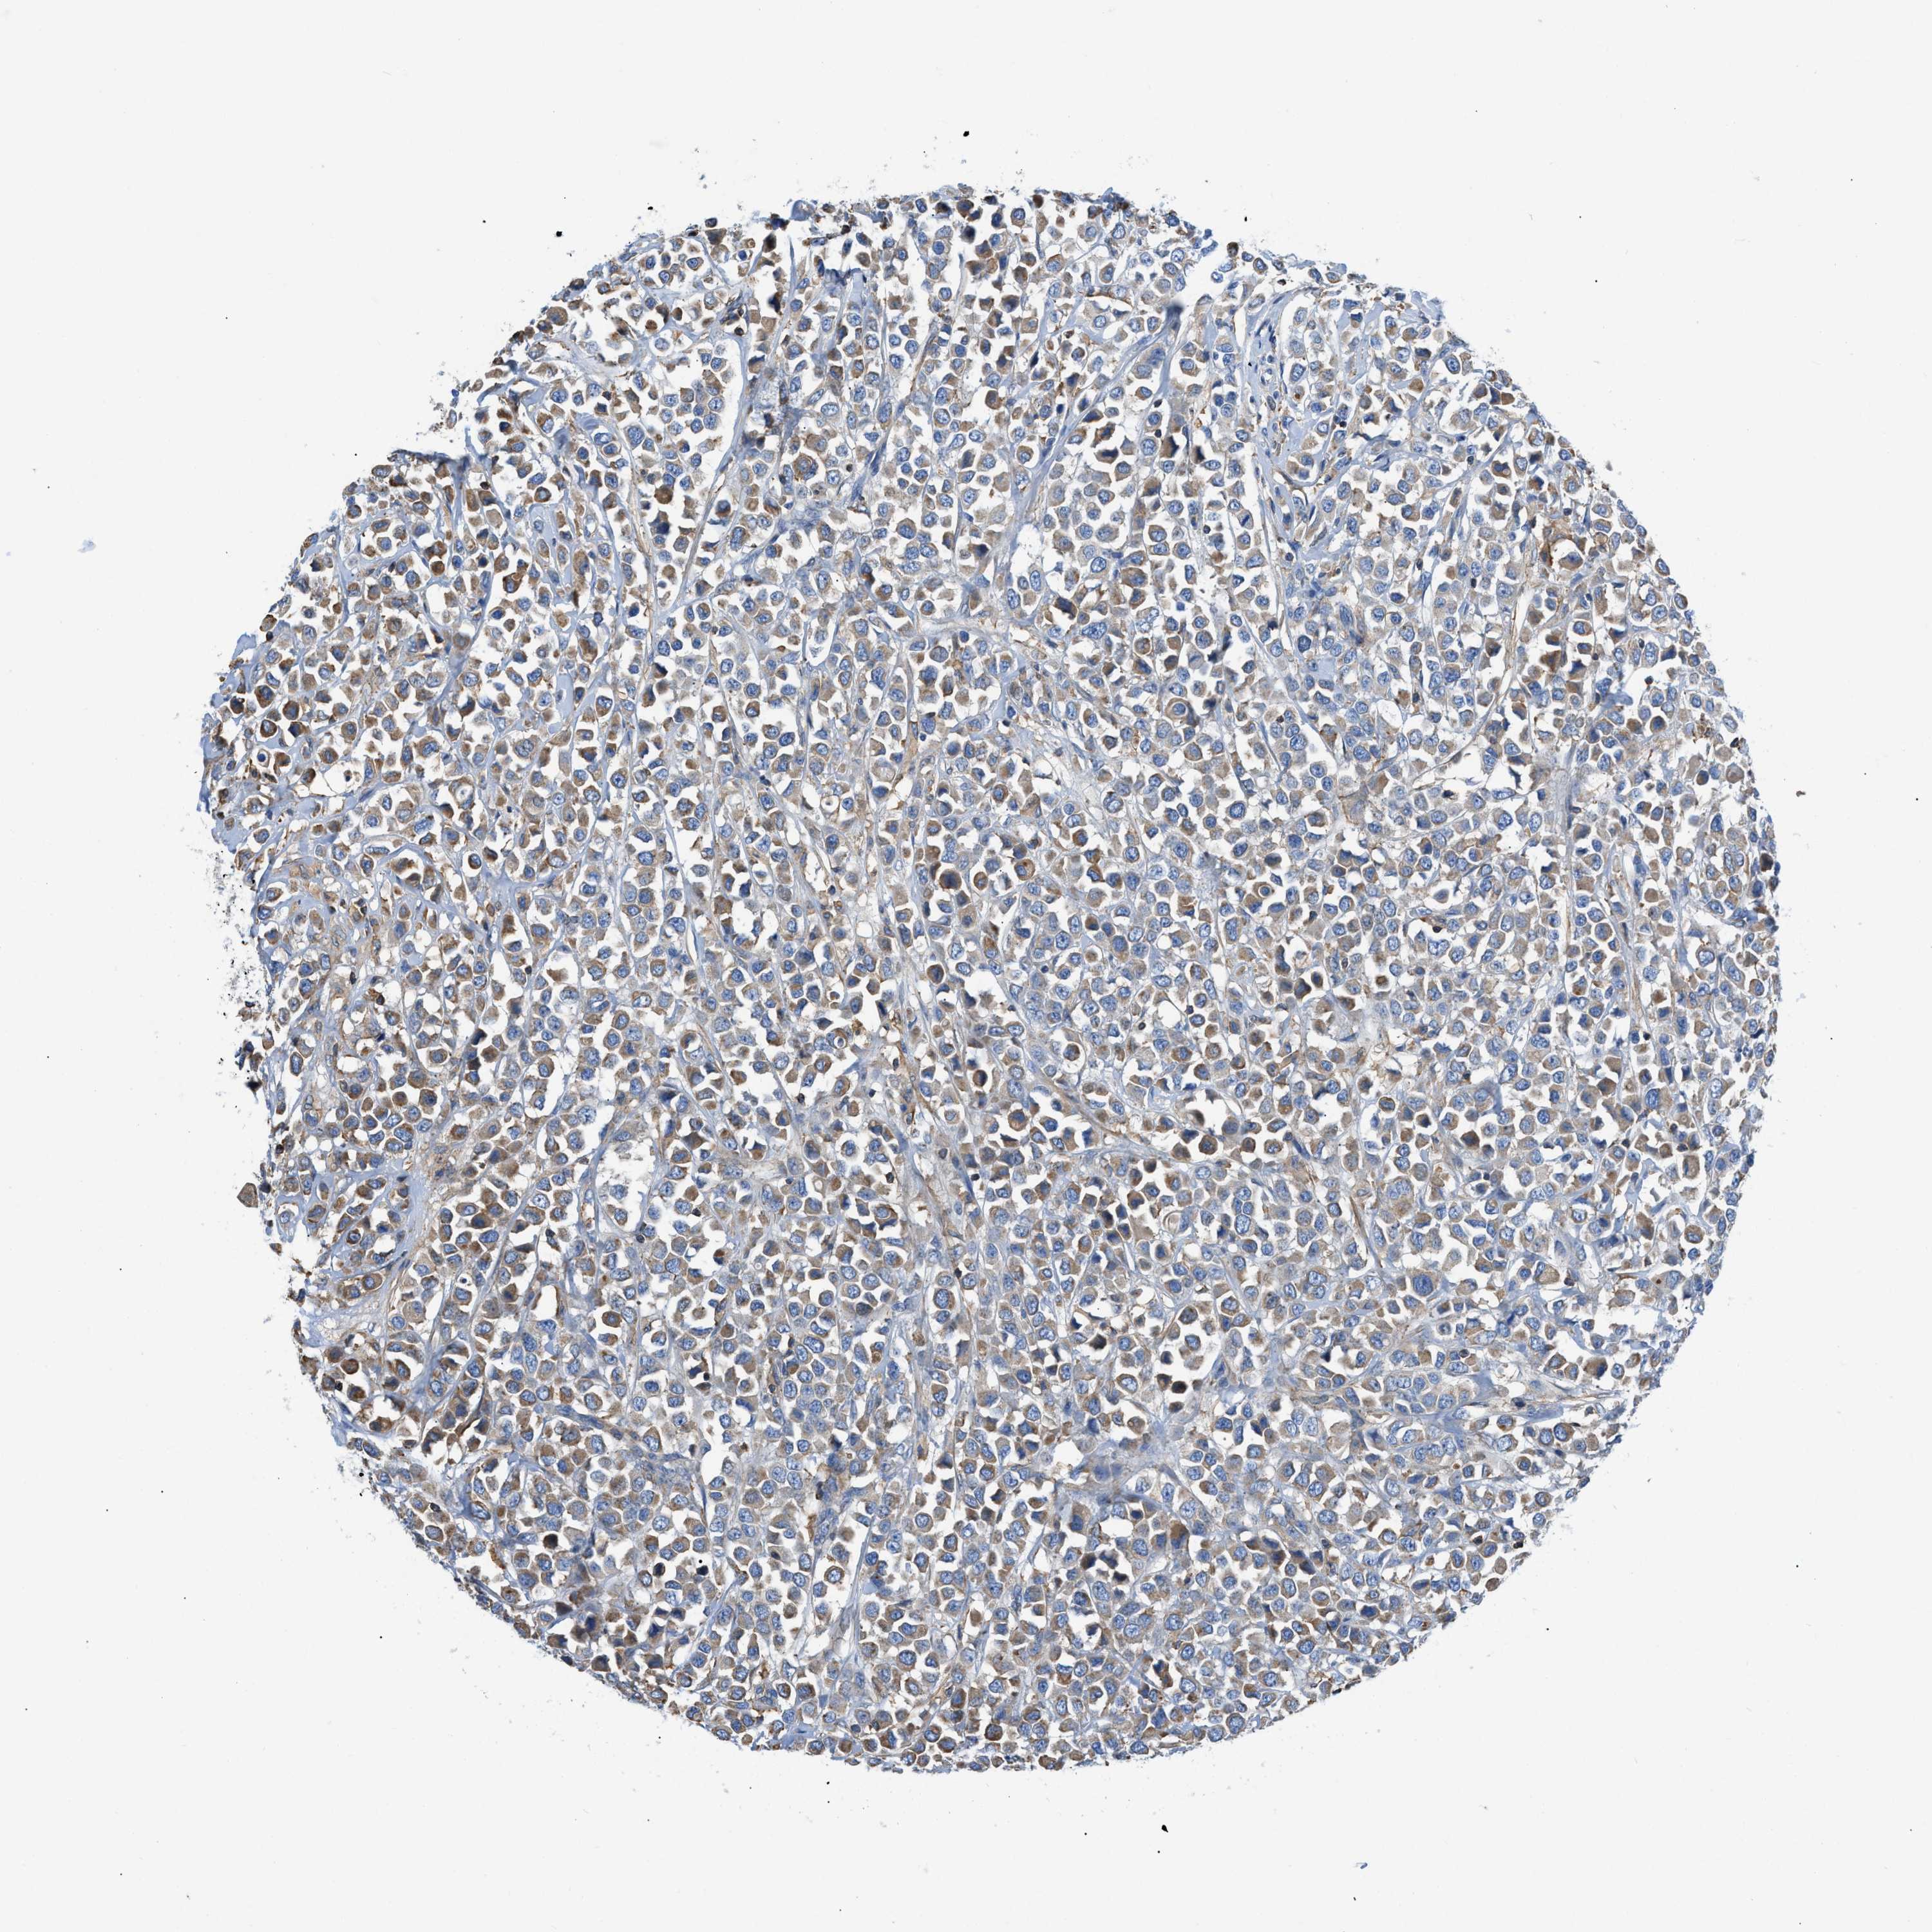

BRCA TCGA BRCA VALIDATION PROTEIN EXPRESSION